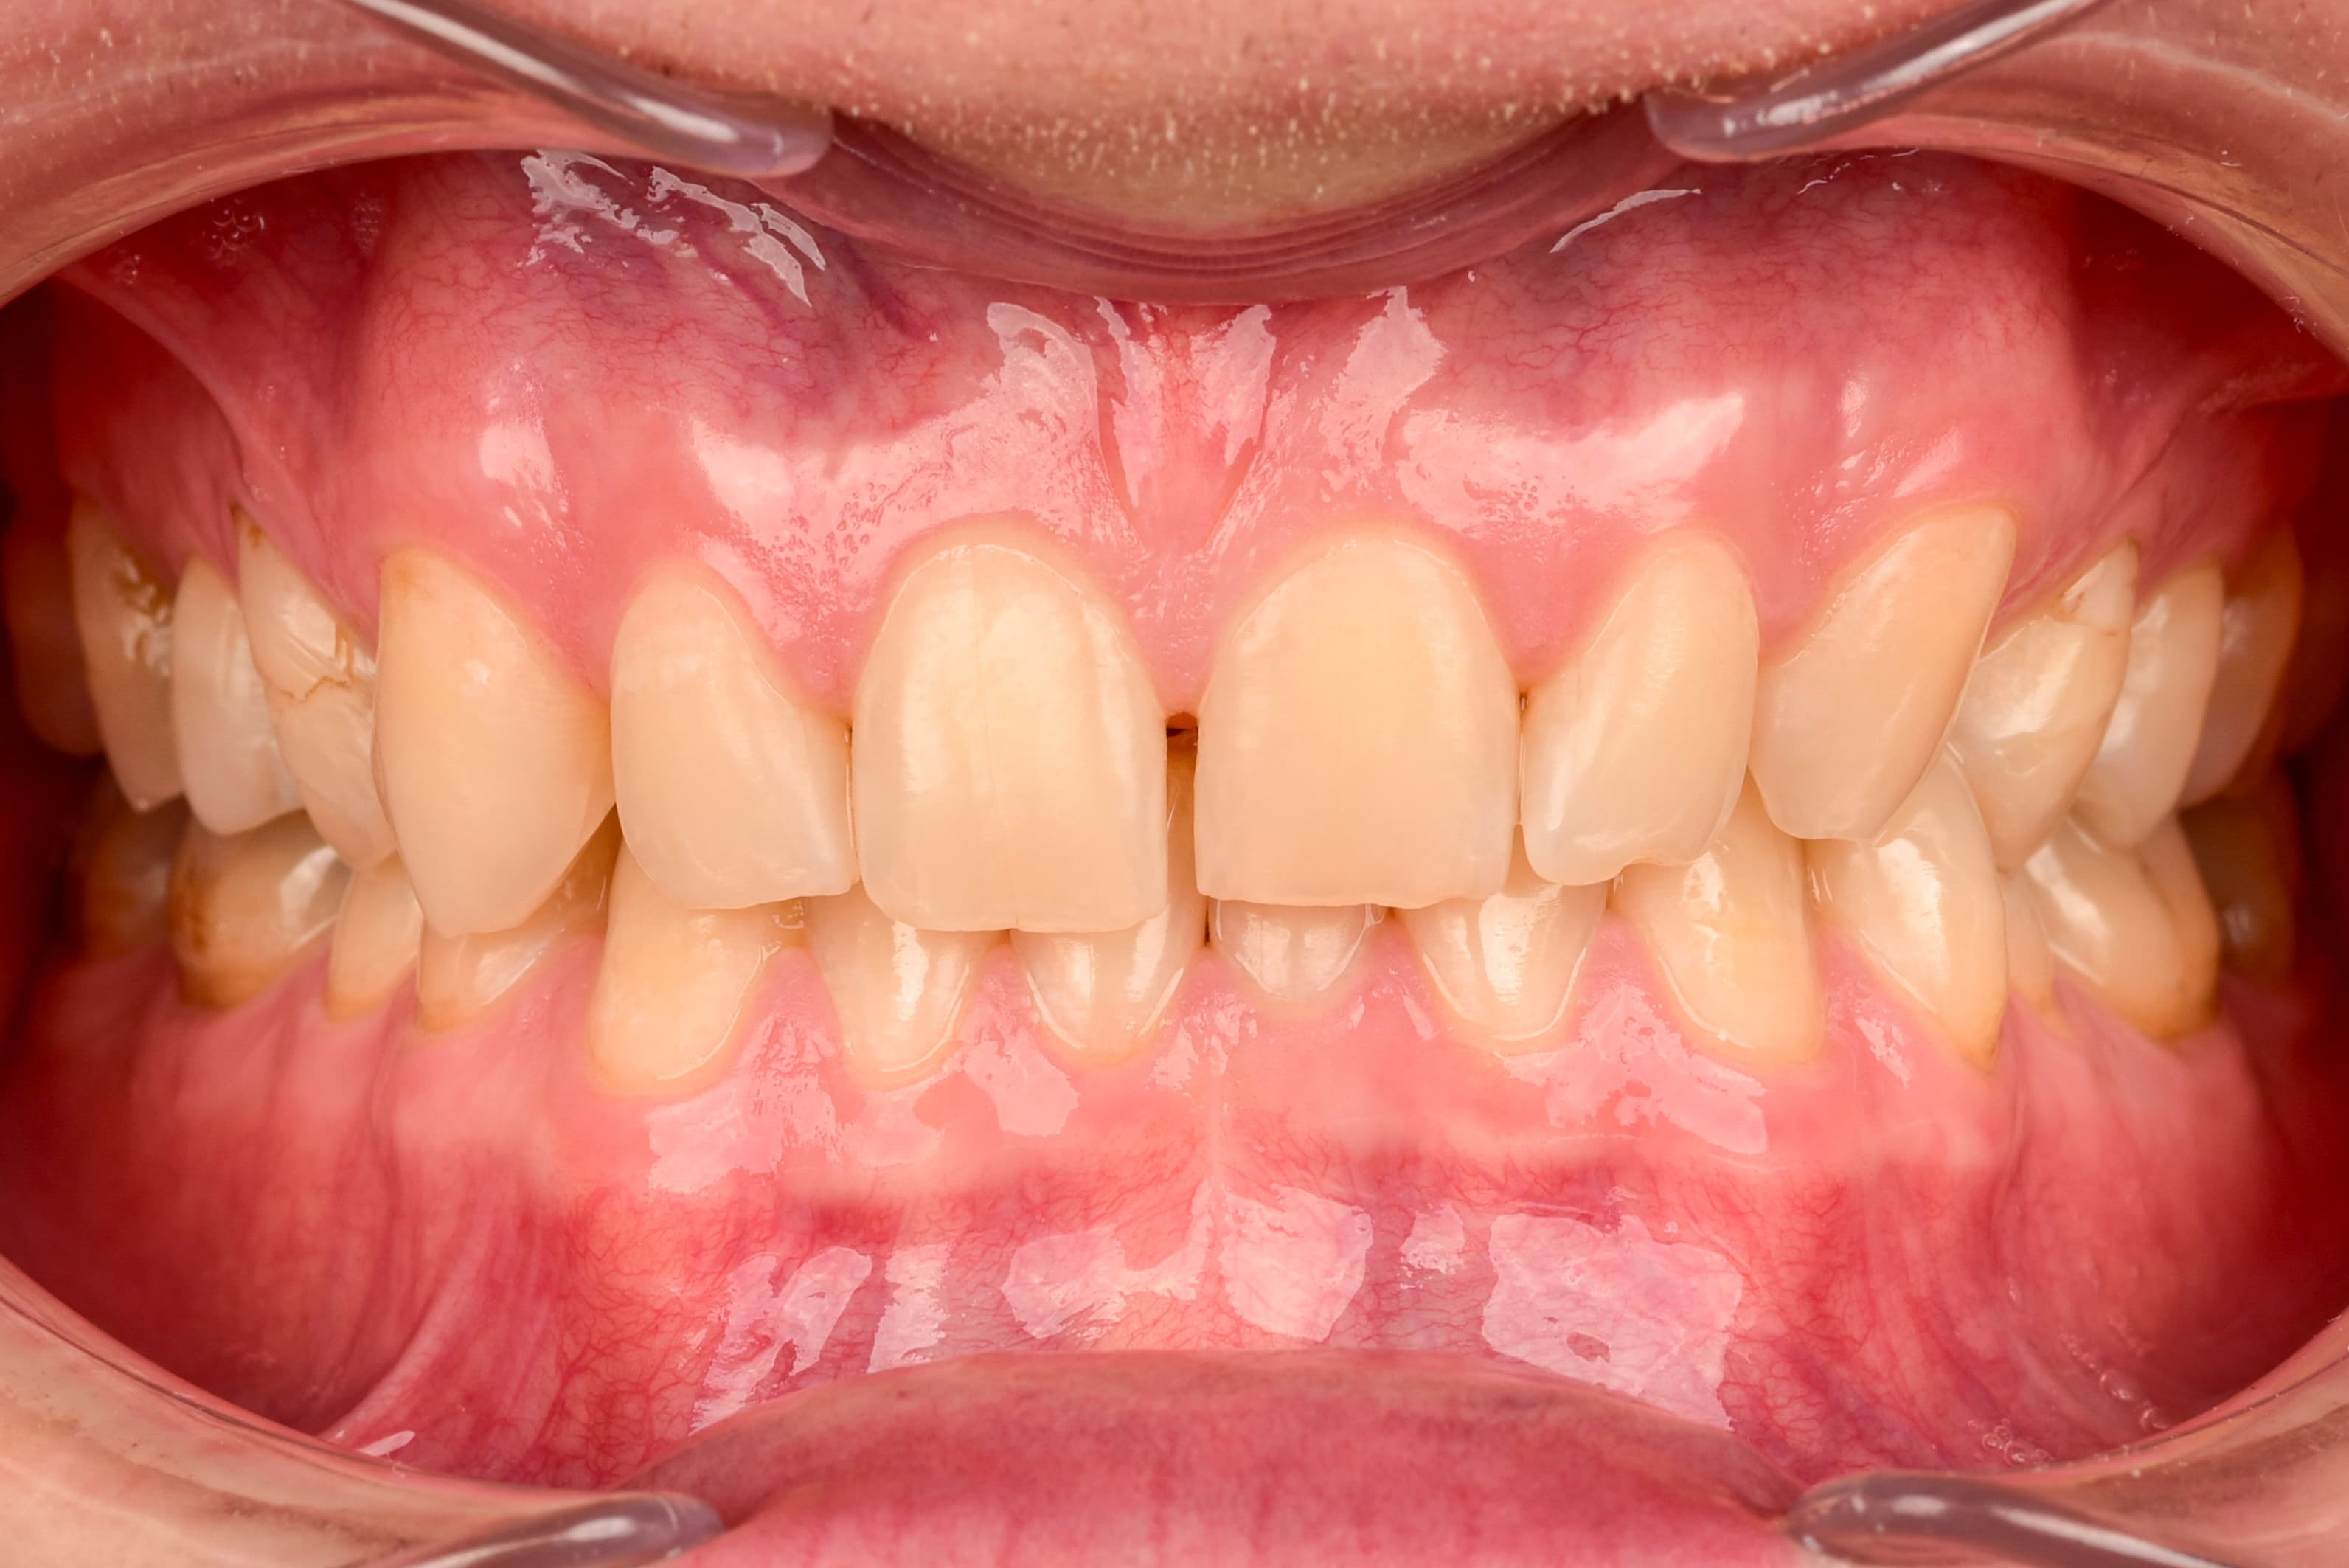

- My gums have become more pink and nicer.

Healthier gums – The disappearance of bleeding, swelling or redness of the gums is a sign that inflammation is decreasing and the oral microflora is returning to balance.

Healthier gum color – A light pink color of the gums is a sign of good blood supply and lack of inflammation.